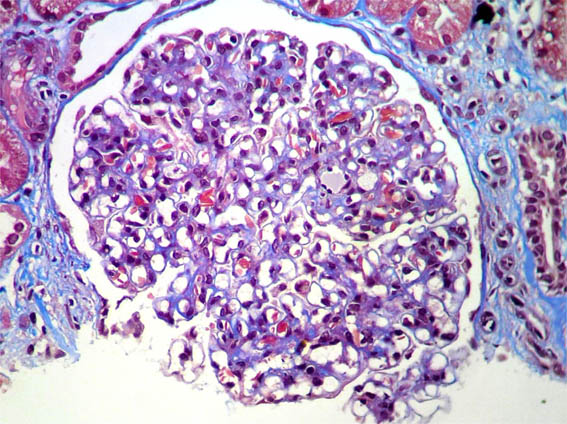

Figure 6.

Masson's

trichrome stain,

X400.